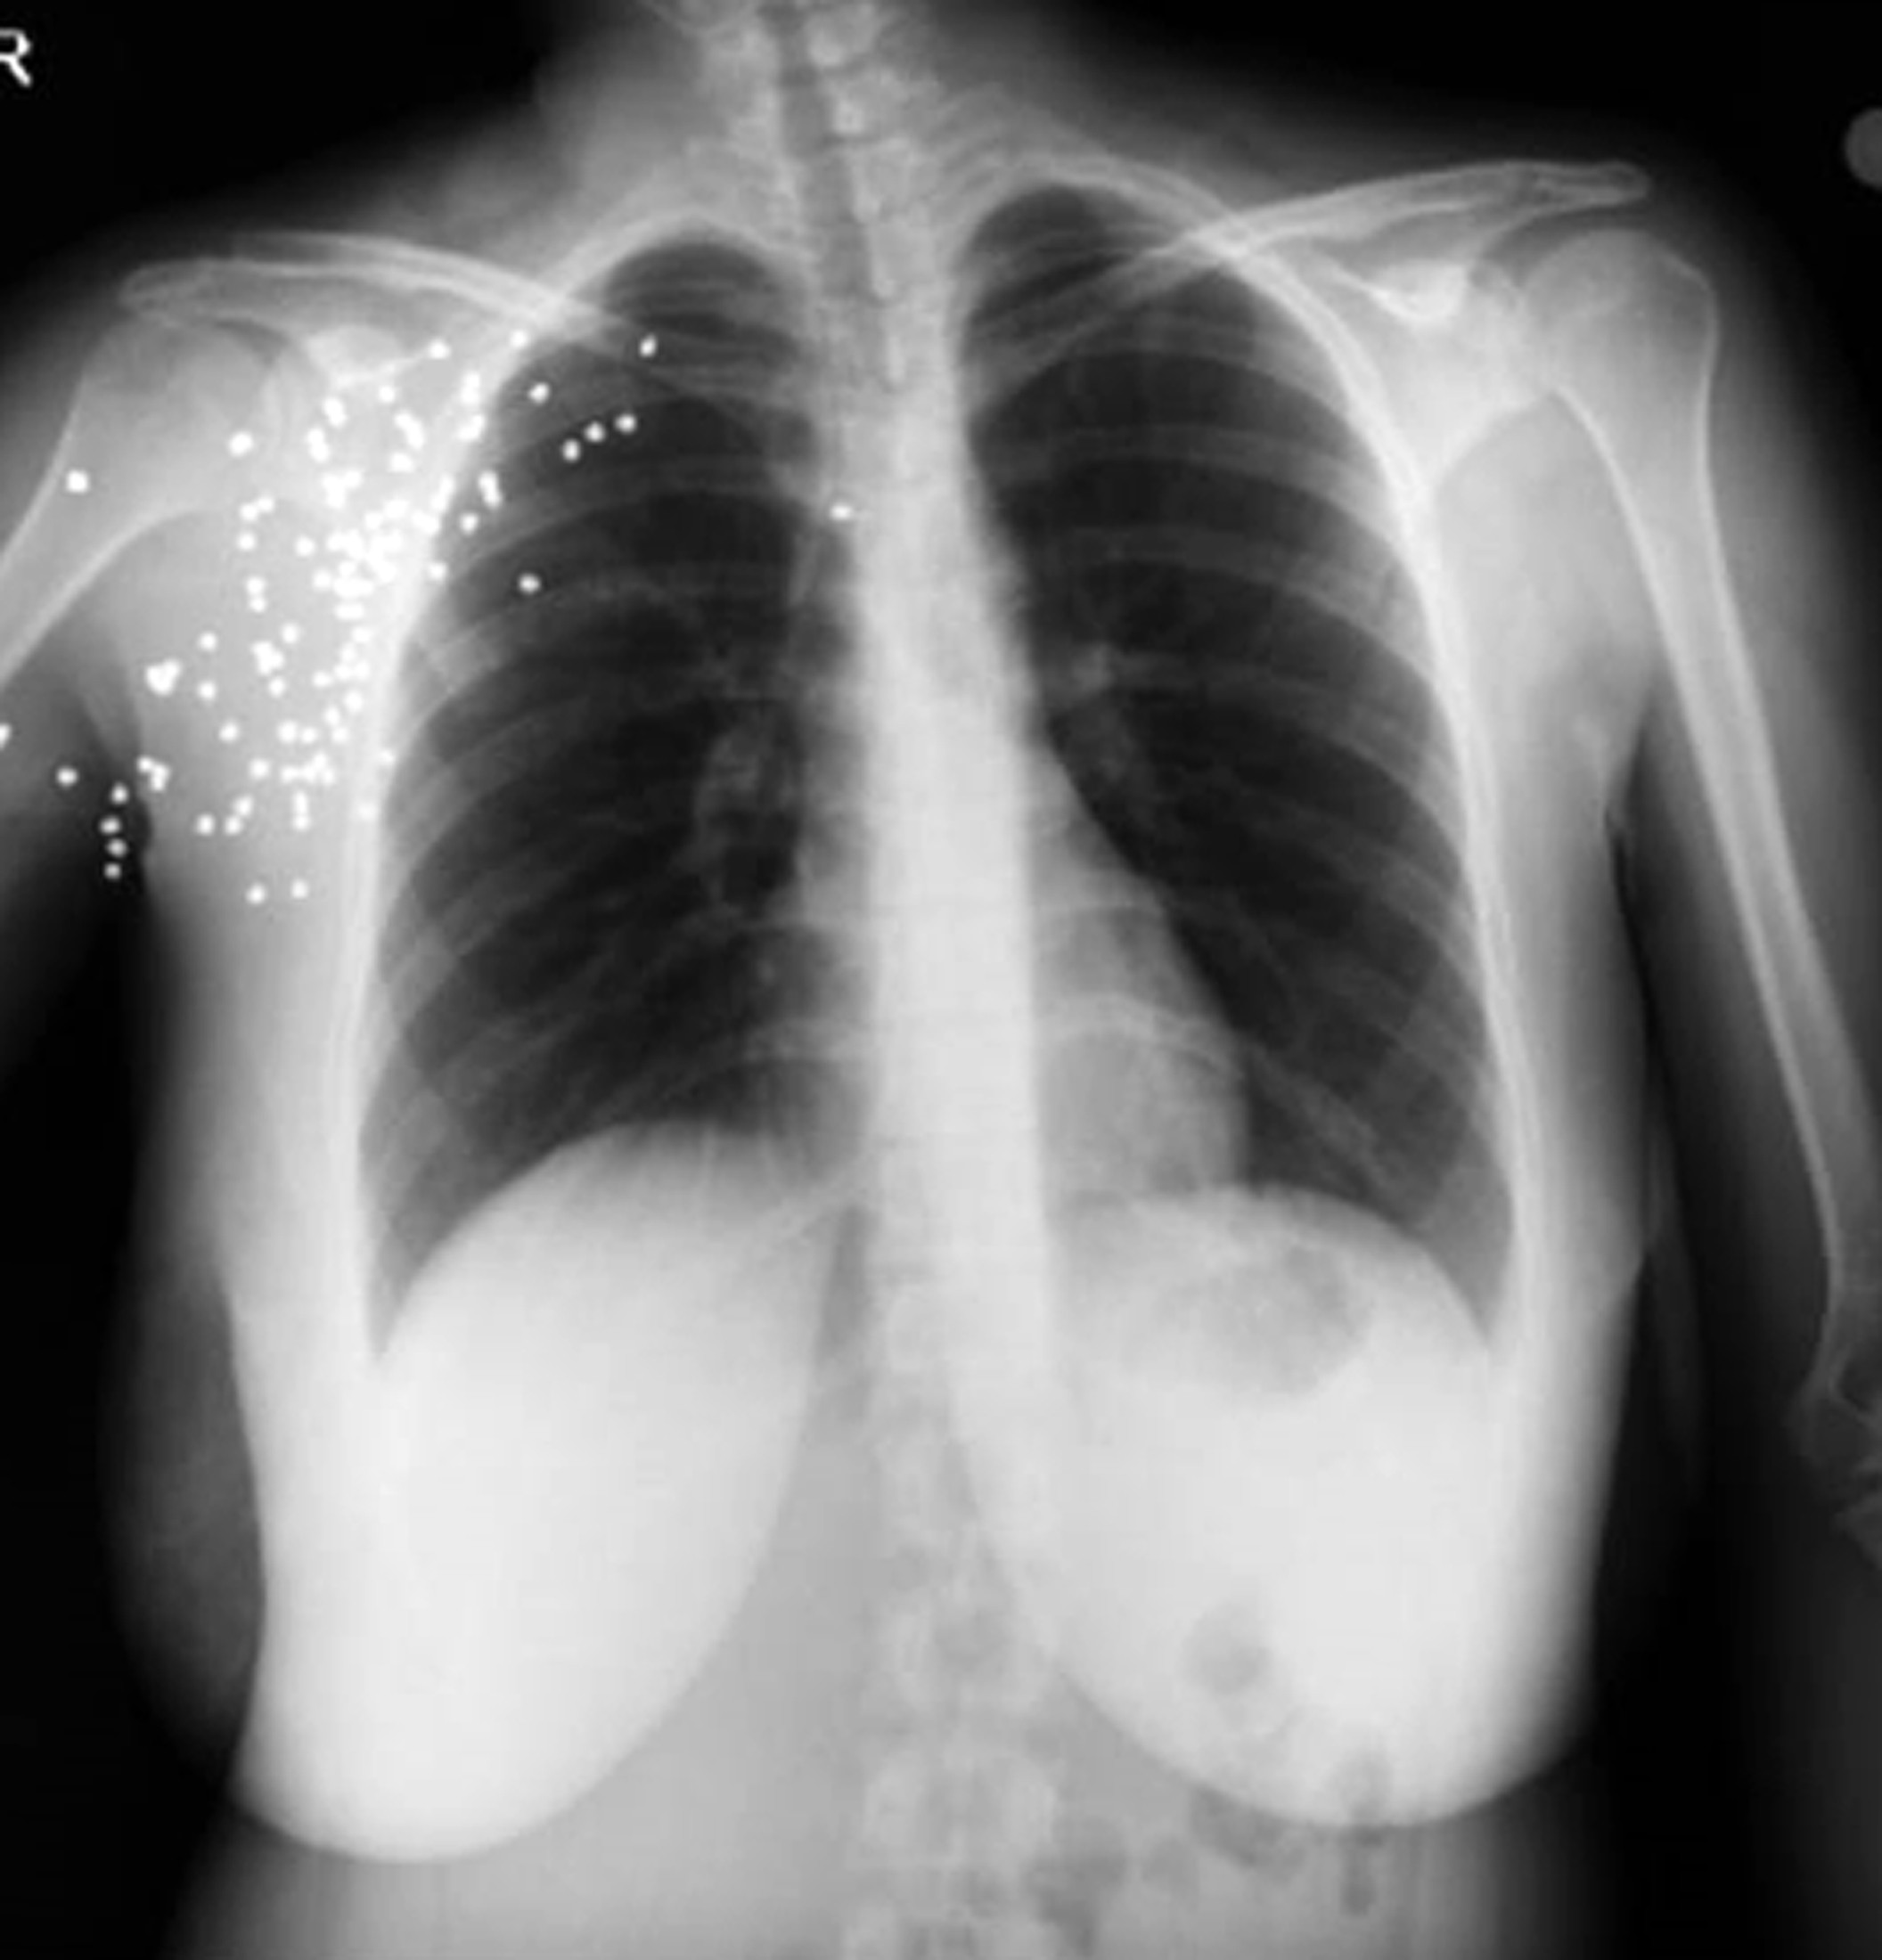

O.D, 30 Ocak''ta Akman''ın ailesiyle birlikte yaşadığı eve saat 06.00 sıralarında geldi. Kapıyı açan Güllü Akman''ın önce ellerini tutup, ardından pompalı tüfeği başına dayayan O.D., eski eşini ve ailesini öldürmekle tehdit etti. Kapıyı kapatmaya çalışan Akman''a, O.D. pompalı tüfekle ateş etti. Sağ kolundan ve omuzundan ağır yaralanan Güllü Akman, hastaneye kaldırıldı. Akman''ın koldan uzanan sinirlerinin koptuğu belirlendi. Gözaltına alınan O.D., serbest bırakıldı.

Hastanedeki tedavisi süren ve 5 kez ameliyat olan Akman''ın kolundaki dikiş yaraları hala iyileşmedi. Sinir kopması nedeniyle sağ bileğini hareket ettiremeyen ve parmaklarıyla birlikte kolunda da his kaybı başlayan 1 çocuk annesi Güllü Akman, 5 ameliyata toplamda 70 bin lira ödedi. Senetle borçlanılan 70 bin lirayı ödeyecek güçleri olmayan Akman ailesi, şimdi de 100 bin liralık yeni ameliyat ile karşı karşıya kaldı.